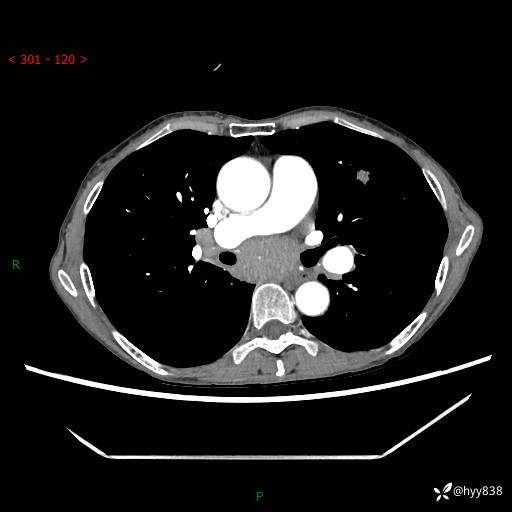

【现病史及既往史】:患者3天余前因既往肺气肿复查胸部CT发现“右肺下叶结节、双肺多发结节、双肺门及纵膈淋巴结增大”,平素偶有咳白色粘液痰,下肢乏力,无明显低热、盗汗、咯血、胸痛、喘气等不适,今为求明显结节性质遂来我院门诊就诊,门诊以“孤立性肺结节”收治入院。 起病以来,患者精神饮食睡眠一般,大小便正常,体力无明细变化,体重近年来较前下降。

【检查】:胸部CT增强